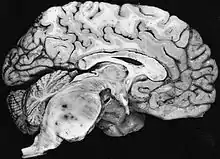

Diffuse fibrillary astrocytomas arising in the brain stem favor the pons: The tumor here produces the classic hypertrophy of the affected region.